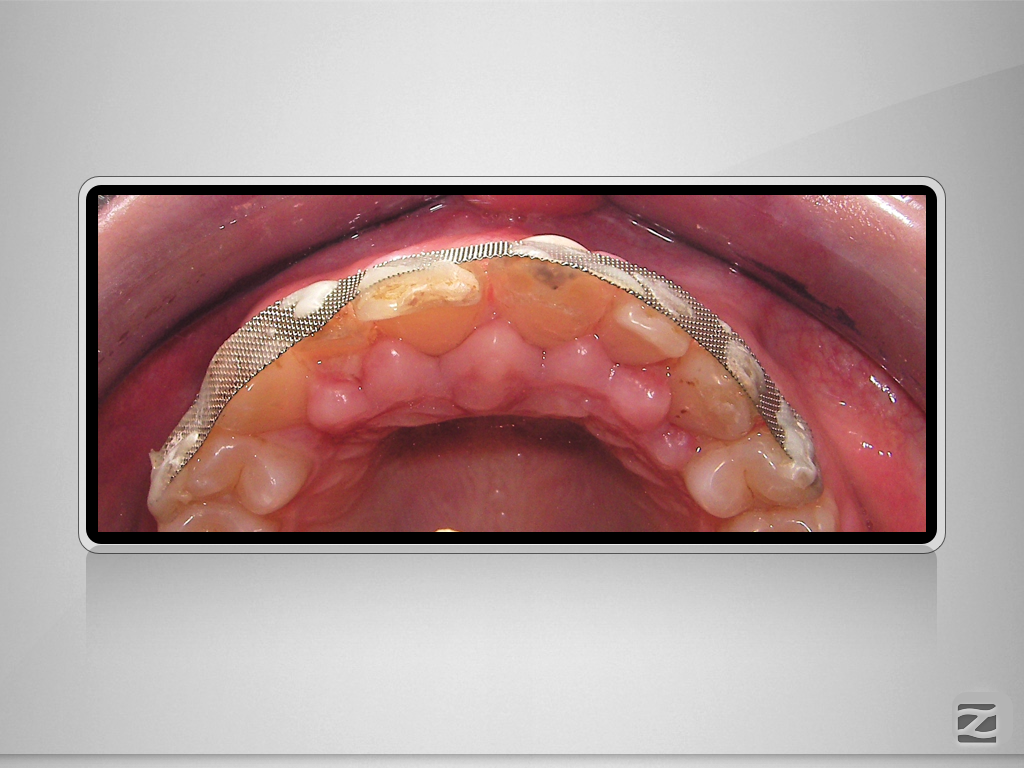

Multitrauma D.004

Mehrfach-Trauma